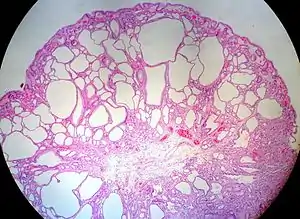

Micrograph of a Peutz–Jeghers colonic polyp - a type of hamartomatous polyp. H&E stain.